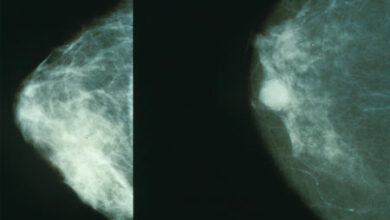

A radiação de curta duração é eficaz para pacientes que optam pela reconstrução mamária após mastectomia

Mamografias mostrando mama normal (esquerda) e mama com câncer (direita). Crédito: Domínio Público Num estudo inédito, pessoas com cancro da…

Ler Mais » - Notícias